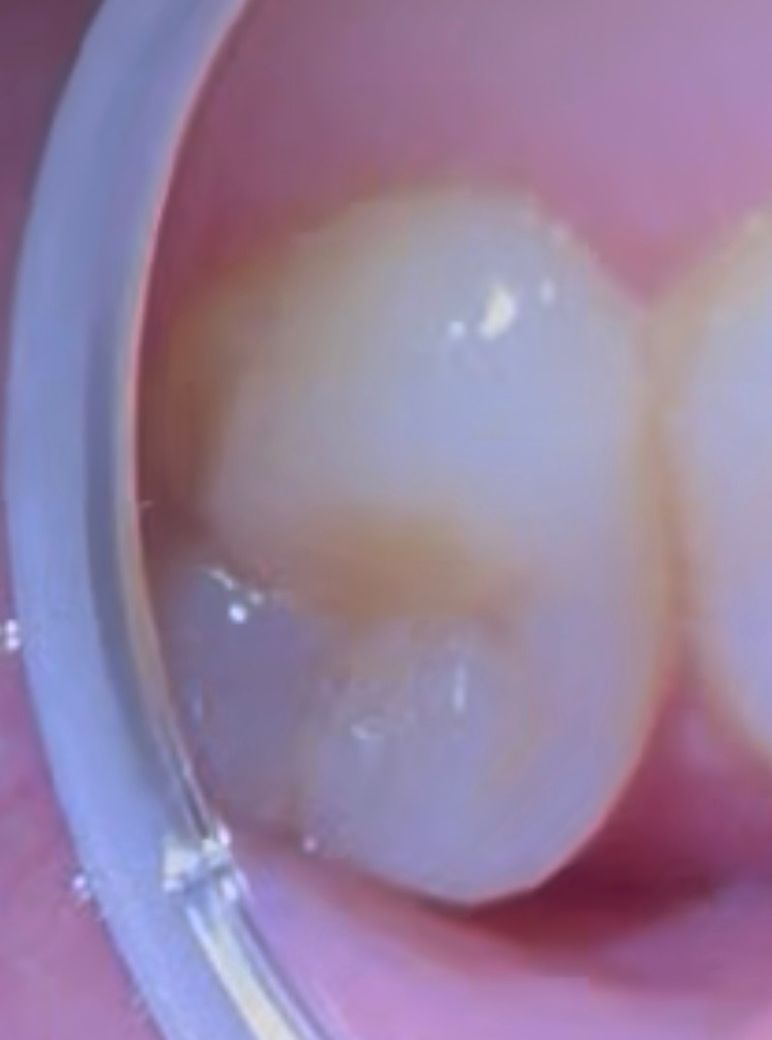

(사진O) 해당 치아의 구멍은 정상인건지 문제인건지 궁금합니다

사진 상 주황 동그라미 부분이 구멍 부분인데요

해당 구멍은 정상인지 문제가 될 수 있을지 궁금합니다

치과에 가셔서 엑스레이도 찍어보고 기구로 눌러 봐야 알수 잇을것같습니다. 사진상으로는 충치가 잇는거 같습니다.

그루브, 열구의 구조인데 약간 탈회(초기 충치)된 것 같습니다. 예방적레진수복(PRR) 적응증일지 치과가서 한번 체크해보시기 바랍니다.